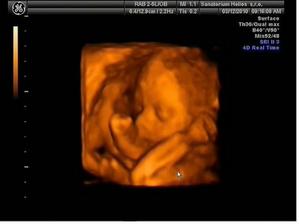

*17.2.10 ultrazvuk v 21tt + kardio ultrazvuk - vše úplně ukázkové :o) hurááá a vypadá to na holčičiku - první Dr. neviděl nic, byla zavrtaná prckou do měkkého a při vyšetření srdíčka se mrkl druhý pan Dr. i mezi nožky a říkal, že vidí holčičku, tak mu to budeme věřit :o) Večer manžel cítil kopanečky na bříšku, bylo to moc pěkný :o)